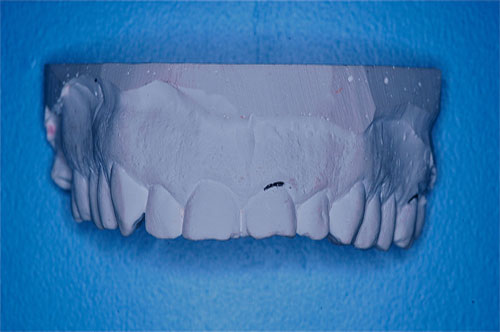

ESTUDIO ESTÁTICO DE LOS MODELOS PREVIOS A LA PRIMERA REHABILITACIÓN APORTADOS POR LA ENFERMA:Modelos Color Blanco

B- ESTUDIO ESTÁTICO DE LOS MODELOS PREVIOS A LA 1ª REHABILITACIÓN APORTADOS POR LA ENFERMA: (La situación oclusal que la enferma tenía antes de que la tocara un dentista (MODELOS COLOR BLANCO)

Diferencias entre ambos modelos:

A nivel de segundos molares= 4 mm +

A nivel de primeros molares= 3,50 mm +

A nivel de incisivo central=5,50 mm +

Luego de observar detenidamente el aumento de altura entre los primeros y los segundos modelos, observamos un detalle que de haberlo visto en primer término, nos habría facilitado enormemente el diagnóstico :

Antes de la 1ª intervención, los segundos molares superior e inferior derechos tocaban.